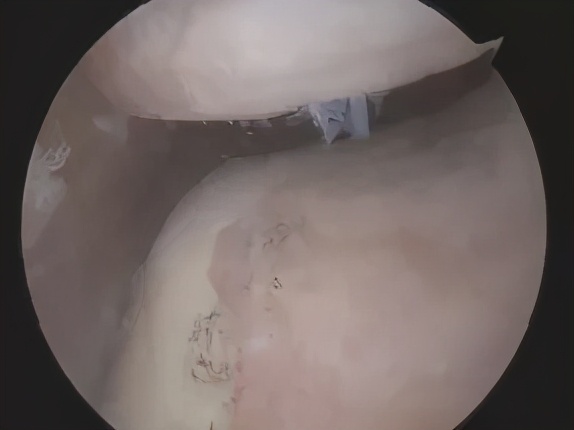

正常的髌股关节

饱经沧桑的髌股关节